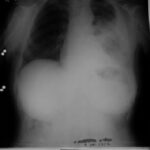

1992 - İlk Başvuru

Sol göğüs ağrısı ve öksürük şikâyeti. Çok düşkün halde.

Teşhis

Malign lenfoma (plevral biyopsi)

Kasım 1992 - Ocak 1993

Röntgende belirgin düzelme. Tümör tamamen kayboldu.

Kasım 1992 (1. Ay)

Röntgende belirgin düzelme görüldü. Tedaviye devam edildi.

Ocak 1993 (3. Ay)

Tümörün tamamen kaybolduğu görüldü.